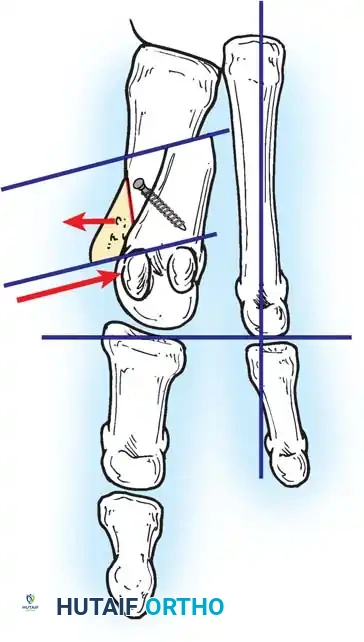

Two other anatomical variants involving the articular surface of the fi rst metatarsophalangeal joint can lead to hallux valgus. In the fi rst variant, the articular surface of the metatarsal head is offset, resembling a scoop of ice cream sitting at an angle on a cone (Fig. 78-6). This has been described as the distal metatarsal articular angle (see Fig. 78-8). In the second, the articular angle of the base of the proximal phalanx in relation to its longitudinal axis is offset. This has been described as the phalangeal articular angle. Although the normal range of these angles is generally considered to be 7 to 10 degrees for the phalangeal articular angle and 10 to 15 degrees for the distal metatarsal articular angle, exact measurements are diffi cult to reproduce because of the variability of radiographic and measurement techniques. Increasing evidence indicates, however, that the failure to correct these two deformities, especially the distal metatarsal articular angle, can cause unsatisfactory results after surgery in some patients. Forceful straightening of the hallux should be avoided if it sacrifi ces tarsalgia. The entire forefoot must be evaluated for these multiple components of hallux valgus before surgical planning is complete and recommendations can be made to the patient. The controversy continues over which deformity is the essential lesion in hallux valgus: metatarsus primus varus or lateral deviation of the great toe. Each is incriminated as the cause of the other. The strongest data probably support lateral deviation of the great toe as the primary deformity in most patients, followed by medial angulation of the fi rst metatarsal, but metatarsus primus varus may be the principal cause in adolescents. Further controversy surrounds the role of footwear as the prime offender in the development of hallux valgus. Most orthopaedic surgeons have seen unilateral hallux valgus when both feet are clinically and radiographically the same structurally except that one foot has a bunion deformity and the other foot is normal. Evidence supports that hallux valgus may be familial, especially when it occurs in adolescents. Although no study of shod and unshod societies has implicated inappropriate footwear as the sole cause of hallux valgus, after genetic factors, binding, unphysiologically designed footwear probably is the major cause in modern societies. Hypermobility of the fi rst ray also has been suggested as a causative factor in the development of hallux valgus and fi rst metatarsal varus, but this is controversial. Coughlin and Shurnas, Myerson and Badekas, King and Toolan, and Faber et al. offer excellent discussions of this problematic area. Finally, certain anatomical and structural abnormalities almost certainly play a causative role in hallux valgus. Pronated fl atfeet, abnormal insertion of the posterior tibial tendon, increased obliquity of the fi rst metatarsomedialcuneiform joint, an abnormally long fi rst ray, incongruous articular surfaces of the fi rst metatarsophalangeal joint, and excessive valgus tilt of the articular surface of the fi rst metatarsal head and proximal phalangeal articular surface may contribute singly or in combination to the deformity and infl uence the recommended treatment. Hypertrophy of the medial eminence has been described as a component of hallux valgus deformity since the earliest reports; however, more recent investigations, including those of Thordarson and Krewer, have found that bony proliferation is not a component of the pathoanatomy of hallux valgus and that the prominence of the medial eminence results from the combination of metatarsus primus varus and medial deviation that uncovers the articular surface. Thordarson and Krewer compared radiographs of 50 feet in patients who had surgery for hallux valgus deformity with radiographs of 50 feet from a control group without hallux valgus deformity and found little difference in the average width of the medial eminence (4.4 mm and 4.1 mm). With more than 130 operations recommended for the treatment of hallux valgus, it is practical to describe only

Fig. 78-6 A, Note valgus orientation of articular surface of fi rst metatarsal head. B, After proximal metatarsal osteotomy on right foot. Sesamoid sling remains dislocated, articular surface of metatarsal head maintains valgus posture, and joint is congruous in valgus. Double osteotomy of fi rst metatarsal (proximally for varus correction and distally for valgus correction of articular surface) and soft-tissue realignment are necessary. Alternatively, arthrodesis of fi rst metatarsophalangeal joint or distal metatarsal osteotomy (chevron) can be performed. Without anatomical reduction of sesamoid sling apparatus, distal metatarsal osteotomy would fail.

A B

Fig. 78-8 A, Determination of position of articular surface of metatarsal head in relation to longitudinal axis of fi rst metatarsal. B, Measurement of distal metatarsal articular angle at time of surgery. Markings are at medial and lateral margins of articular surface of fi rst metatarsal head and longitudinal axis of fi rst metatarsal shaft. metatarseum between the bases of the fi rst and second metatarsals might preclude the effectiveness of a soft-tissue procedure alone to provide suffi cient correction of the increased intermetatarsal angle. Likewise, accessory sesamoids and prominent ungual tuberosities at the interphalangeal joint contribute to a painful callus at the tibial side of this joint. An os tibialis externum frequently is associated with excessive hallux valgus interphalangeus. Varus of the fi rst metatarsal might be a signifi cant part of the overall deformity of the foot even with an intermetatarsal angle of less than 10 degrees. Metatarsus varus with a relatively small hallux valgus angle (15 to 20 degrees) may produce signifi cant deformity even though the angles are not excessive. The usefulness of computer-assisted compared with manual measurement of the intermetatarsal angle, hallux valgus angle, and distal metatarsal articular angle is still uncertain. Both methods have closer interobserver and intraobserver correlation in measurement of the intermetatarsal angle and hallux valgus angle than in measurement of the distal metatarsal articular angle. The reliability of either method has such a wide range (5 degrees), however, that measurements of these angles, although useful as a guide, do not provide a completely reliable indication of the magnitude of deformity. Condon et al. suggested that the reliability of the intermetatarsal angle can be improved by careful technique and by making the measurements at least twice and averaging them. Schneider et al. reported two methods of determining angular measurements based on distinctly different reference points: (1) a longitudinal axis of the fi rst metatarsal using middiaphyseal reference points, and (2) a center-head technique using a center head (center of the articular surface) and center base

(center of the proximal diaphysis) as reference points. They found that measured correction of the hallux valgus and intermetatarsal angles varied by approximately 9 degrees depending on which reference points were used. Recommendations of Coughlin, Saltzman, and Nunley (American Orthopaedic Foot and Ankle Society Ad Hoc Committee on Angular Measurements) included standardized radiographic technique, specifi c placement of reference points (Fig. 78-11), use of a protractor rather than a goniometer for measurements, and, after distal osteotomies, dual measurements using a center-head technique and a Mose sphere.